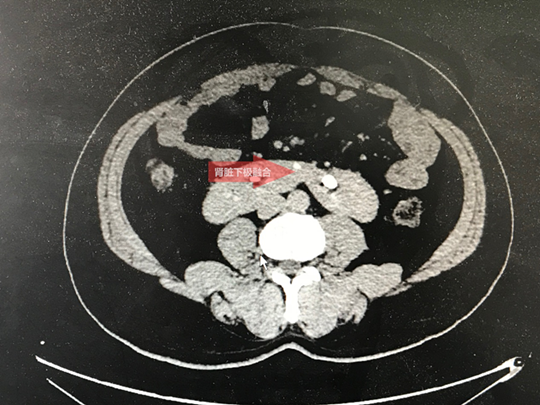

11月25日上午,我科收治了一位“马蹄肾”的患者。49岁的朱先生,沭阳七雄人,既往有肾结石病史,曾多次在外院碎石治疗,但治疗效果均不满意。因为腰部疼痛反复发作,朱先生感到痛苦不堪。患者入院后查CTU提示马蹄肾、左肾巨大结石。正是由于朱先生的马蹄肾、肾脏发育畸形,导致其在外院多次治疗均失败。

肾脏是人体的重要器官,普通人的肾脏有两个,左右两边各一个,并且相互独立。但是,有些人的两个肾脏是连在一起的,如字母“U”。这种病症,在医学上被称为“马蹄肾”。 马蹄肾是两侧肾脏的上极或下极相融合成马蹄,是一种先天性发育畸形。马蹄肾因肾脏旋转不全、肾血管多畸形、输尿管高植入、跨越峡部而受压,因此易引起肾积水、尿路结石及继发感染等,其中尿路结石最常见。

马蹄肾合并肾结石的治疗方法比较棘手。传统开放手术创伤太大,出血量较多,愈合时间延长。该患者U形肾畸形,但肾积水又很少,肾脏周边被腹腔脏器包绕,若行微创经皮肾镜取石术,术中可以穿刺的间隙很小,手术很容易引起肾血管和腹腔脏器损伤,对术者B超引导下穿刺技术要求非常高。手术风险极高,取石手术难度巨大。